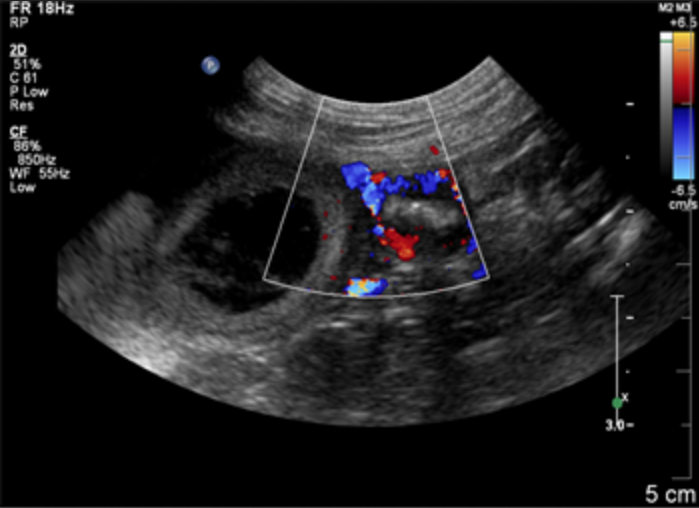

Узи кишечника собаки

Узи кишечника собаки 84 фото